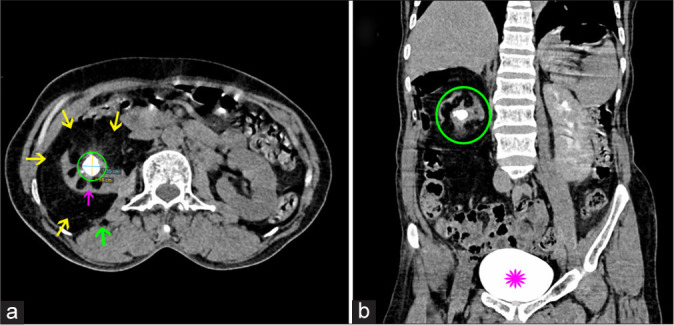

Renal replacement lipomatosis (RRL), as described by the word, is characterized by abnormal proliferation of the fatty tissue and replacement of renal parenchyma by fat with atrophy of renal parenchyma. This rare condition is mainly attributed to a long-standing disease such as lithiasis. The patient usually presents with non-specific abdominal pain of chronic duration, and imaging is necessary to confirm the diagnosis. Here, we present the case of total RRL presented at our center, diagnosed with ultrasonography, and computerized tomography of kidneys, along with contributing factors and its course of treatment.